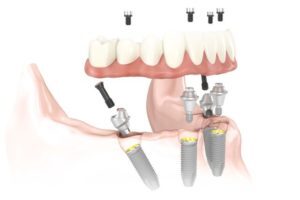

La técnica All-on-Four aprovecha el hueso denso que permanece en la parte frontal de los maxilares (superior e inferior) y colocando los dos implantes posteriores en ángulo para evitar las cavidades sinusales en el maxilar superior y el canal nervioso en el maxilar inferior.

En el pasado los especialistas considerábamos que eran necesarios entre 6 y 10 implantes para suministrar suficiente estabilidad a una rehabilitación con implantes fija de arco completo. La nueva tecnología ha encontrado que si los implantes finales se colocan con una determinada angulación, su fuerza se incrementa drásticamente. Esto nos permite ser capaz de anclar un puente fijo con tan sólo 4 o 6 implantes – mucho menos de lo que se utiliza normalmente. Colocar menos implantes también ahorra mucho dinero. Además, los implantes y los nuevos dientes se colocarán en la misma visita